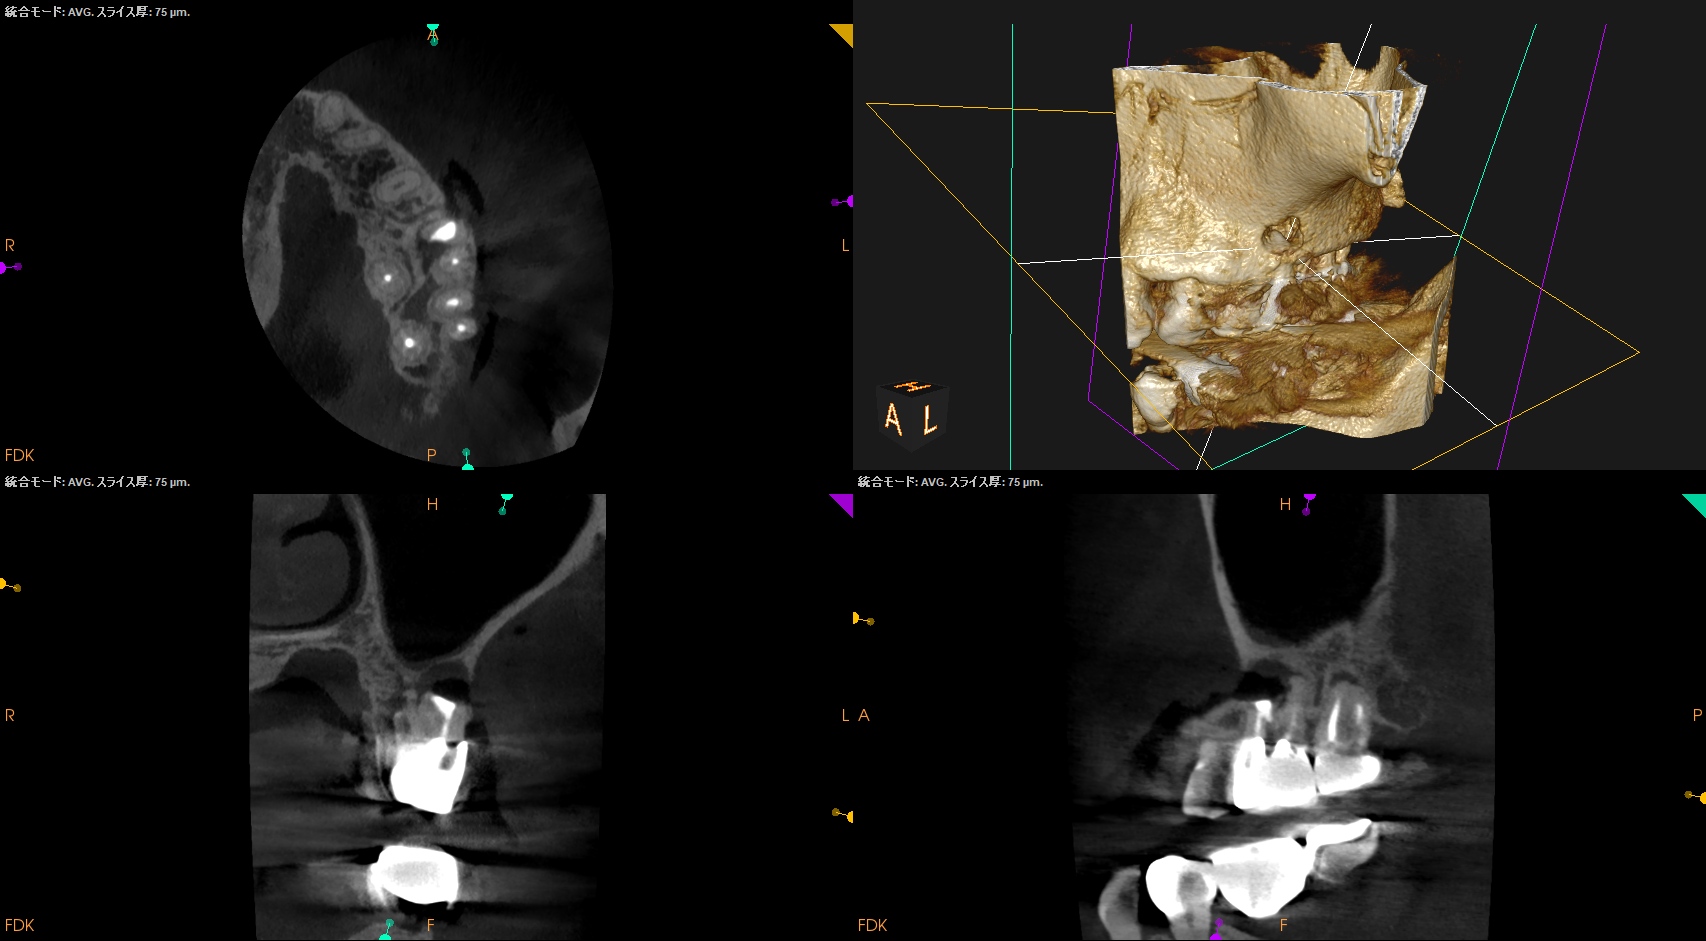

術後にPA, CBCTを撮影した。

後日、築造するがその後のPAが以下だ。

MB

B

逆根管充填材は逆根管形成で穿孔させたが即日修復=充填しているので問題ないだろう。